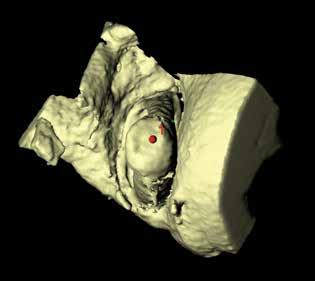

MicroCT and 3-D reconstruction. Images of the 20 temporal bones from the 10 selected crania were obtained on a microCT device (Inveon MicroCT; Siemens Healthineers; Erlangen, Germany). Since the gross physical sizes of the temporal bones exceeded the imaging aperture of the scanner, the specimens were physically reduced. The microCT images were then made with a pixel size of 20 × 20 μm, a slice thickness of 21.5 μm, and a resolution of 46.499 pixels/mm.

First, each stapes was cropped from the surrounding structures and ambient air by hand. Second, the “background noise” was subtracted. Third, the image stack was processed with the Isosurface algorithm of BoneJ, which converts the stack into a triangular surface model. The surface model was saved into a Standard Tessellation Language (STL) file format for dimensional analysis of the stapes structure. Fourth, the 3-D viewer was used to visualize the STL models. Reference points were marked directly on the 3-D models and recorded as x, y, and z coordinates.

Stapes measurements. The stapes height was calculated by measuring the distance between a point in the center of the top of the capitulum and a point in the center of the stapes footplate on the medial (vestibular) surface (figure 1). The footplate’s length was calculated by measuring the distance between points on both ends of the long axis of the footplate annulus. The footplate’s width was calculated by measuring points on both ends of the short and long axes of the footplate annulus.

After we created the models in BoneJ, we identified each landmark in 3-D space (x, y, and z) with the point tool. For measurements of the footplate length, we used the landmarks that represented the farthest point on the “big toe” side of the footplate and the farthest point at the “heel.” For footplate width, we determined the widest diameter perpendicular to the footplate length. Footplate dimensions were thus determined in a manner analogous to a shoe salesman measuring a foot (figure 2). Each measurement was performed twice, independently. Calculations and statistics. Distance measurements were calculated according to the Pythagorean theorem in three dimensions. Only if associations were suggested on scatterplot graphs were nonparametric Spearman correlations calculated. No correction for multiple comparisons was done.

Figure 1. MicroCT shows a right stapes viewed from a surgeon’s perspective, laterally onto the superstructure. Note the footplate’s socked-foot appearance, with the big toe anterorinferior. The red circle (1) indicates the center of the top of the capitulum.

Figure 2. MicroCT demonstrates a right footplate viewed onto the vestibular (medial) surface. The red circles denote the center of the footplate (2), the limits of its length (3), and the limits of its width (4) perpendicular to the length.